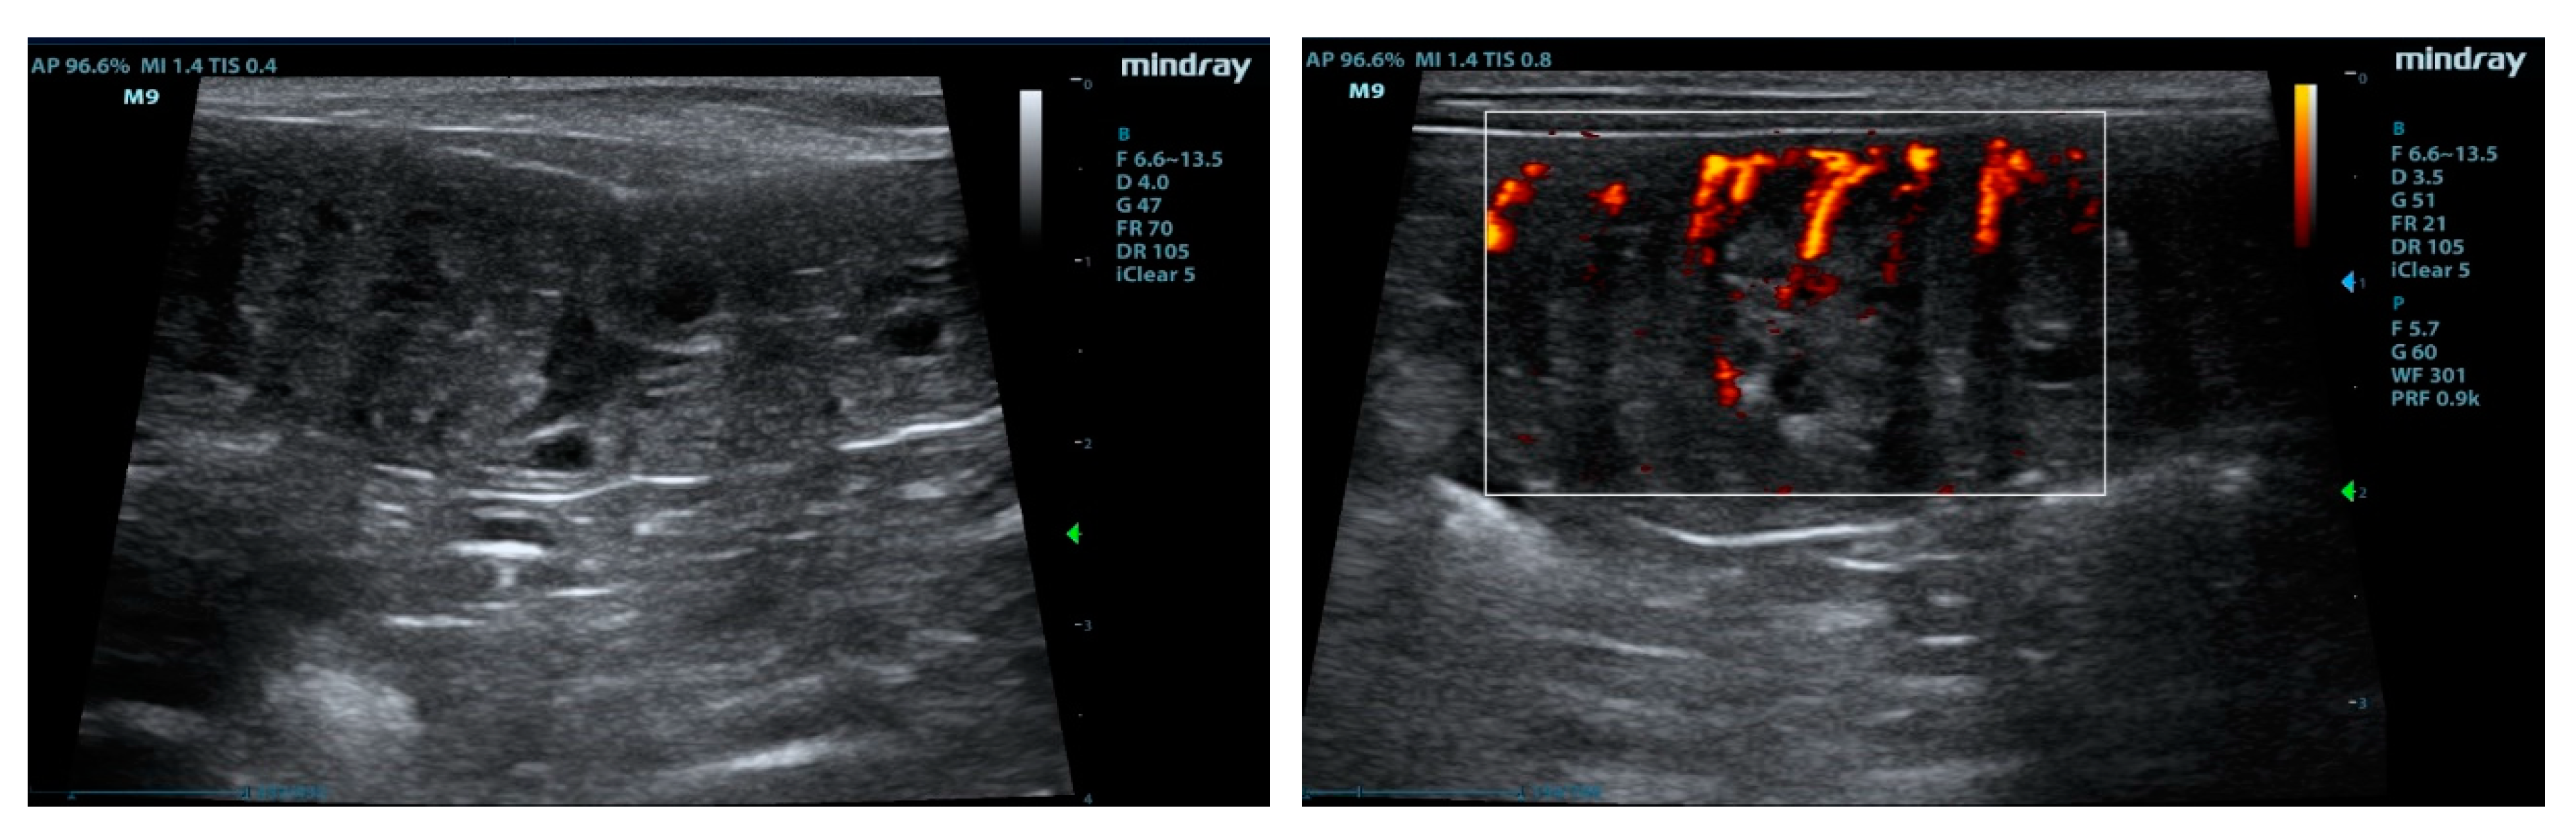

2.3. B-Mode, Color Doppler and Contrast-Enhanced Ultrasound Procedures

2.4. Imaging Analysis

3.1. Ultrasonographic Examinations